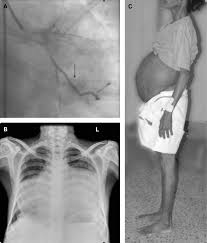

Cardiac Cachexia (CC) syndrome, is a complication of CHF(Congestive Heart Failure)

it is a sign of bad prognosis. and related to age, sex , LV ejection fraction and exercise capacity.

it happen when generalized lose of body lean mass, tissues, fat and skeletal. Therefore, patient is weak and very weak, asthenic syndrome.